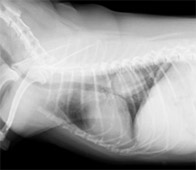

肝臓腫瘍

病名:肝細胞癌 手術法:内側右葉完全肝葉切除術

症例:11歳 避妊雌 MiX犬 12kg

主訴:1週間前から食欲の低下と嘔吐で来院されました。

検査:腹部超音波検査にて肝臓内側右葉に直径約12cm大の肝臓腫瘍が認められました。また、胆のうに重度の胆泥の貯留を認めました。